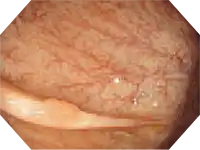

NBI in EVIS EXERA III 190 series scopes provides twice the viewable distance of EVIS EXERA II 180 series scopes and offers much greater contrast between blood vessels and mucosa. The greatly improved performance of NBI opens up exciting new clinical applications and reinforces NBI’s position as the standard of care for GI endoscopy.

White light NBI

Image courtesy of Tonya Kaltenbach, MD